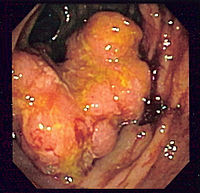

Endoscopy

A colonoscopy is the best test for making the diagnosis of Crohn's disease as it allows direct visualization of the colon and the terminal ileum, identifying the pattern of disease involvement. Occasionally, the colonoscope can travel past the terminal ileum but it varies from patient to patient. During the procedure, the gastroenterologist can also perform a biopsy, taking small samples of tissue for laboratory analysis which may help confirm a diagnosis. As 30% of Crohn's disease involves only the ileum, cannulation of the terminal ileum is required in making the diagnosis. Finding a patchy distribution of disease, with involvement of the colon or ileum but not the rectum, is suggestive of Crohn's disease, as are other endoscopic stigmata.The utility of capsule endoscopy for this, however, is still uncertain.